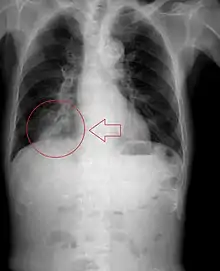

| Aspiration of corn kernel that became lodged in the airway of an adult patient. | |

Radiography is the most common form of imaging used in the initial assessment of a foreign body presentation. Most patients receive a chest x-ray to determine the location of the foreign body.[2] Lateral neck, chest, and bilateral decubitus end-expiratory chest x-rays should be obtained in patients suspected of having aspirated a foreign body.[6] However, the presence of normal findings on chest radiography should not rule out foreign body aspiration as not all objects can be visualized.[2] In fact, up to 50% of cases can have normal findings on radiography.[7] This is because visibility of an object depends on many factors, such as the object's material, size, anatomic location and surrounding structures, as well as the patient's body habitus.[13] X-ray beams only show an object if that object's composition blocks the rays from traveling through, making it radiopaque and appearing lighter or white on the image. This also requires it to not be stuck behind something that blocks the beams first.[13] Objects that are radiopaque include items made of most metals except aluminum, bones except most fish bones, and glass. If the material does not block the x-ray beams it is considered radiolucent and will appear dark which prevents visualization.[13] This includes material such as most plastics, most fish bones, wood, and most aluminum objects.[13]

Signs on x-ray that are more commonly seen than the object itself and can be indicative of foreign body aspiration include visualization of the foreign body or hyperinflation of the affected lung.[13] Other x-ray findings that can be seen with foreign body aspiration include obstructive emphysema, atelectasis, and consolidation.[8]